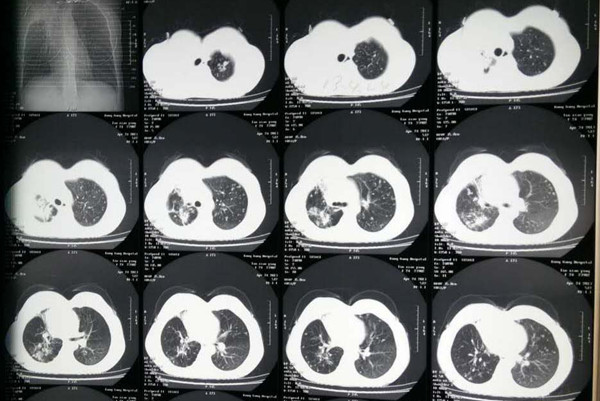

首先我们先来看下什么是肺结核?肺结核是由结核杆菌侵入人体后引起的一种具有强烈传染性的慢性消耗性疾病,它不受年龄、性别、种族、职业、地区的影响。各类人群均可发病,当患者感染结核疾病后如果不及时治疗,那么就会通过咳嗽、打喷嚏,使带有结核杆菌飞沫喷出体外,让健康人吸入后而被感染。

那么如何早期发现肺结核疾病呢?一般来说肺结核早期症状主要是咳嗽、疲乏无力、食欲减退、消化不良、消瘦、盗汗等症状,如果连续咳嗽两周且症状仍然不减轻,那么就需要及时去定点医疗机构检查,下面我们就来看下肺结核怎么治疗?